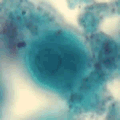

A 32-year-old woman from Sudan submitted a stool specimen as part of a general

physical examination. She was a refugee from Sudan and had been

living in a holding camp in the Middle East before relocating to Texas.

The woman’s health was compromised because of poor living conditions,

including inadequate sanitary facilities and exposure to animals.

The parasitology lab at the Texas Department of Health, Bureau of Laboratories

identified the organism shown in Figures A and B. Figure

A was captured from a direct wet mount prepared from a formalin

preserved specimen and stained with Lugol’s iodine. Figure B,

which simulates focusing through four different planes, is a series

of four individual images of the same organism from a PVA stool smear

stained with the trichrome stain. The objects ranged in size from

10 to 18 micrometers in diameter. What is your diagnosis?

Based on what criteria?